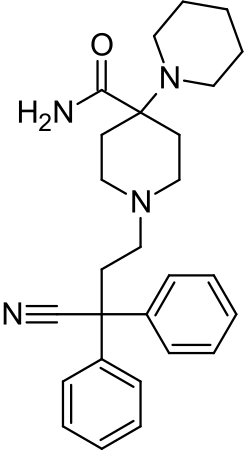

| Formula | C27H34N4O |

| Molar mass | 430.596 g·mol−1 |

| 3D model (JSmol) | |